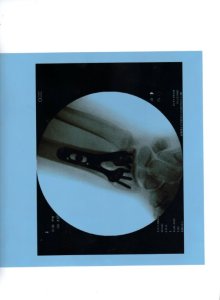

So, yesterday at noon I made my way to the surgery center and had my 4th piggie, the one that had none, shortened, tendons moved, arthritis dug out, and a temporary pin inserted. All of that took, according to Cutie Pie, ten minutes. Now never mind, that I went hours and hours and yet even more hours without morning coffee, it was worth it. Granted, I am on pain pills, but even with a heavily bandaged foot and a pin, mind you, a pin, I am experiencing less pain. Plus I get to stay home from work for a few days.

The downside is the sexy surgical sandal I must wear for two weeks. Oh. And the pin sticking out of the top of my foot. If you look at the photo of my foot at the beginning of this post closely enough you can see the pin.

Go ahead and laugh. I did and so did she. She even laughed when she found it was broken in two places and required surgery. She laughed during pre-op and laughed post-op. She laughed when she viewed the x-ray showing her dandy new titanium plate and pins.